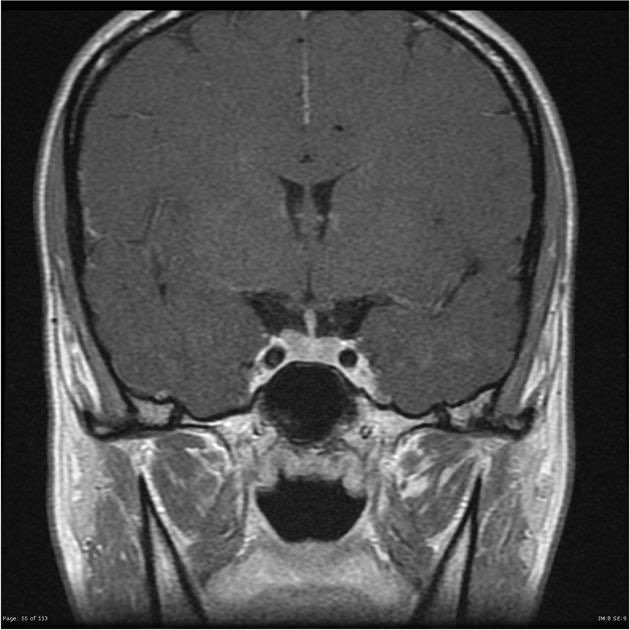

Img | Sellar MRI: Pituitary mass |

• Hyperprolactinemia가 무월경의 원인으로 추정된다. Prolactin 수치가 많이 높으며, sellar MRI상 pituitary mass가 확인된다. Prolactin < 200 ng/mL이기는 하지만 MRI finding으로 보아 prolactinoma로 추정된다.

다음은 참고를 위한 normal pituitary gland를 보여주는 brain MRI의 coronoary view이다.